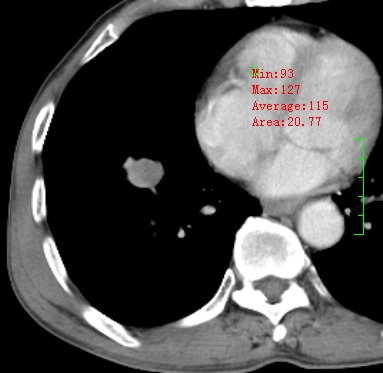

m,73y。膝关节疼痛伴双下肢水肿。入院常规胸片发现结节灶。增强为静脉期。

指套征,强化明显,近侧肺组织局限性肺气肿,考虑支气管类癌,慢支、肺气肿、双上陈旧性tb、冠脉钙化。

1)考虑右肺下叶周围型肺癌。2)右肺上叶及左肺感染性病变(结核可能)。3)肺气肿。4)冠状动脉钙化。